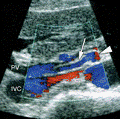

Əməliyyatdaxili ultrasəs müayinəsi 5MHz T tipli linear və ya əyri transdüser ilə aparılır (şək.1)

müayinəni aparan radioloq cərrahi sterilizasiyaya uyğun şəkildə əməliyyatda iştirak edir.

Transabdominal müayinələrdən fərqli olaraq US gel yerinə normal fizioloji məhluldan istifadə olunur. Ilk olaraq qaraciyər anatomik quruluşu müəyyən edilir (seqmentlər, damarların anatomiyası, öd yollarının variantları və s.) (şək.2)

Sonradan isə patoloji prosesin yerləşmə nahiyyəsi, yayılma dərəcəsi, damarlara olan münasibətini,invaziya dərəcəsini və  rezeksiya olunacaq sahənin adekvat olub olunmamasını müəyyən edilir.

Damarların anatomiyası və qan axının ölçülməsi rəngli Doppler müayinəsi ilə aparılır (şək.3).

Intraoperativ US müayinəsi transabdominal US müayinəsi ilə müqayisədə daha sensitiv və spesifikdir (98 və 95% təşkil edir).

Əməliyyatdaxili US müayinəsi ilə preoperativ MR müayinəsi arasında da fərqlər mövcuddur, belə ki MR müayinəsi zamanı sensitivlik 86,7% olunca US müayinəsinin sensitivliyi 94,3% çatır.

Trifazik KT müayinəsi ilə müqaisədə, intraoperativ US spesifikliyi və sensitivliyi demək olar ki eynidir, hətta 50% xəstələrdə intraoperativ US müayinəsi cərrahlara əlavə informasiyanı verilməsi haqqında yazılarda var, bu da öz növbəsində 15% hallarda öncədən planlaşdırılan cərrahi taktikasının dəyişdirilməsinə gətirib çıxarıb.